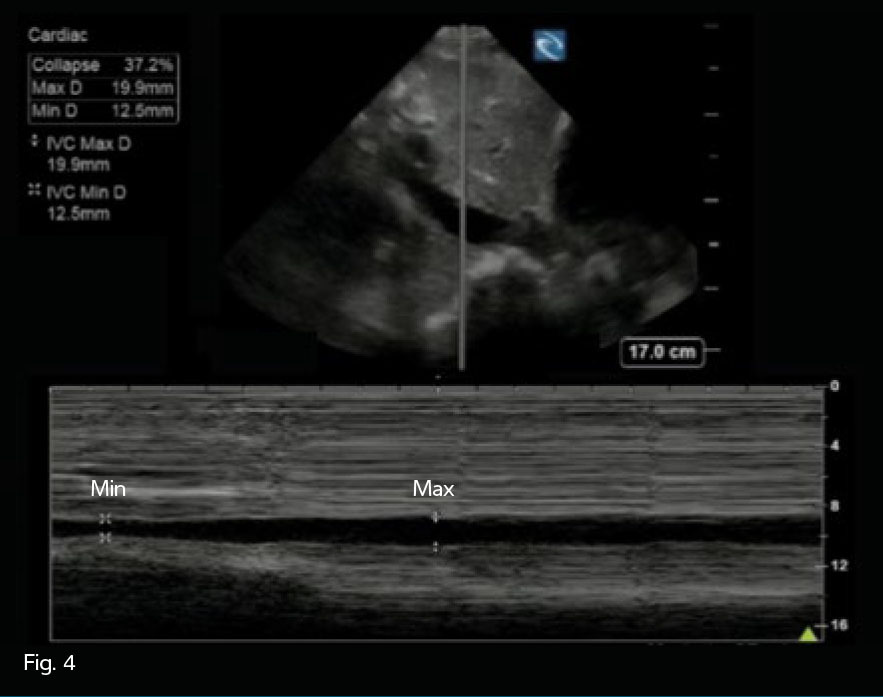

IVC Fig. 4